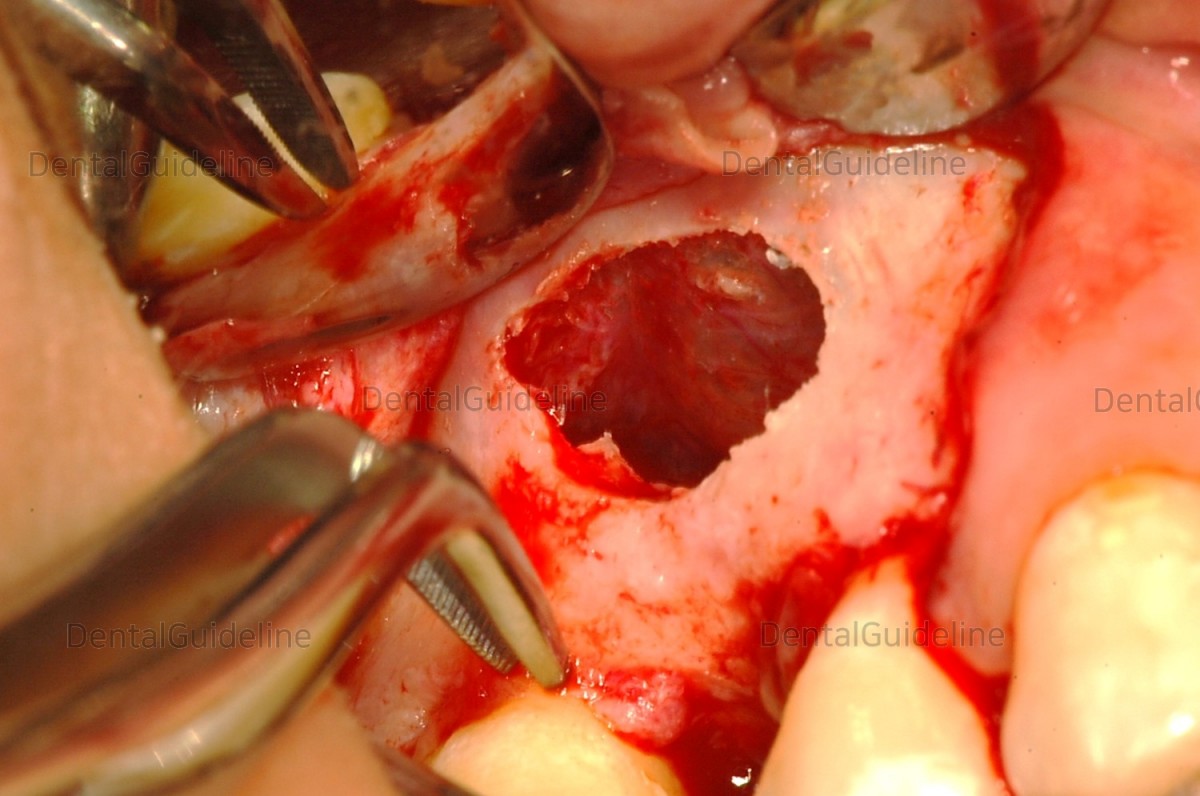

3. For the laterally approached maxillary sinus graft, the

lateral window was opened using a Pizo piezo surgical equipment

(SURGYBONE®, SIILFRADENAT Co,)

4. AIO(All-In-One) sinus curette was used.

5. The maxillary sinus membrane was sufficiently raised.